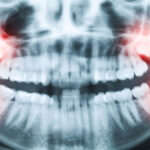

An endodontist focuses on the tooth’s pulp and root. Root canal therapy, retreatment of failed root canals, and small root surgery fall to the endodontist. That specialist trains beyond dental school to work at a microscopic level inside the tooth. When pain points to the nerve or an X-ray shows an infection near the root tip, the endodontist is the right call.

Endodontists often use a microscope. It magnifies tiny canals and reveals hidden branches that are easy to miss. Advanced imaging helps find infections and plan treatment precisely. Those tools increase the chance of success in tricky cases.

Lingering pain, sharp pain with hot and cold, or pain that wakes at night often suggests a nerve issue. A dark spot on an X-ray near the root tip also points to infection. If a prior root canal continues to cause trouble, specialist retreatment is often needed.